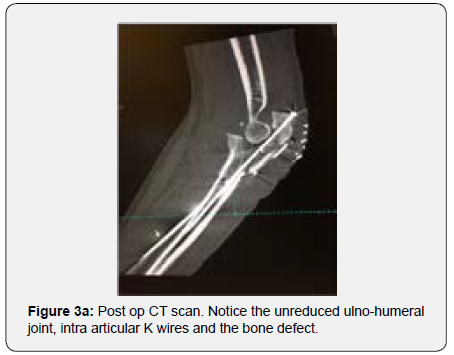

In order to better evaluate the injury and to plan corrective surgery, a CT scan was performed confirming the unreduced comminuted proximal ulna fracture and greater sigmoid notch bone loss with subsequent radio capital subluxation (Figures 3a & 3b) After disussing the case with the patient, decision was made to perform a surgical revision of the osteosynthesis using a tricortical iliac bone graft as the bone gap present seemed to prevent adequate articular stability and bone healing.